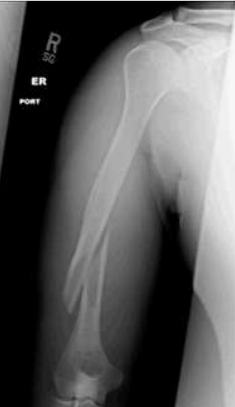

57.22歲男性於軍中練習投擲手榴彈時,採用錯誤的過頂投擲(overhead throwing)方式,在擲 出手榴彈後,感到右上臂劇烈疼痛,送醫照射X光片結果如下圖。關於此種骨折型態,最容 易合併何種神經傷害?

(A)正中神經(median nerve) (B)橈神經(radial nerve) (C)尺神經(ulnar nerve) (D)腋神經(axillary nerve)